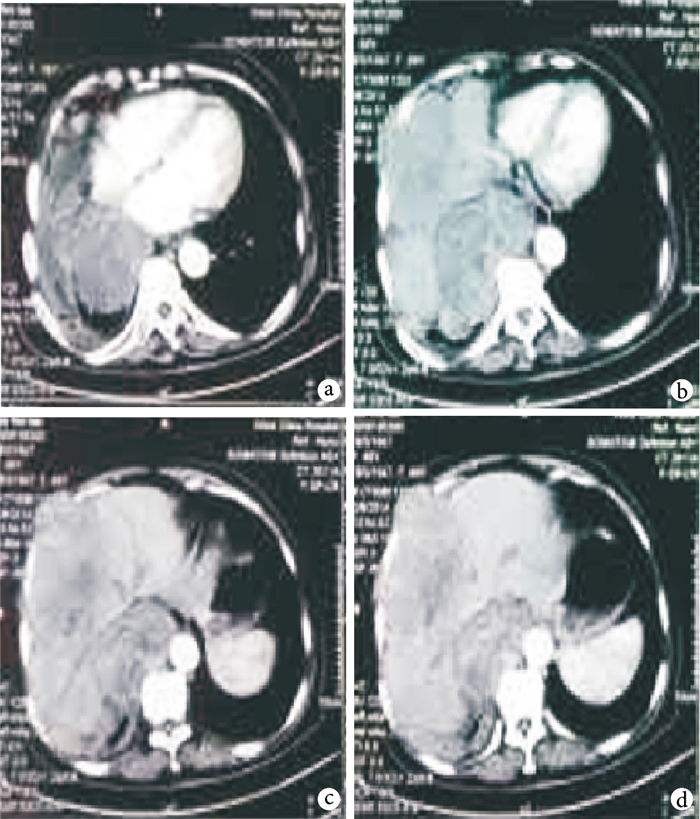

a~d.從4個不同層面展示右縱隔-胸腔區域多發軟組織結節及腫塊伴不均勻強化,與胸膜分界不清,部分腫塊侵犯右胸壁下份,向下推壓肝臟變形

患者??女,66歲。2003年2月于外院行胸部X線檢查發現右縱隔小包塊,無發熱、呼吸困難等不適,未予以特殊處理;既往慢性支氣管炎、腦梗死病史,無糖尿病病史及家族史。2006年5月開始反復發作低血糖,夜間為主,表現為大汗、眼花、頭暈、神志不清,進食后緩解,于外院行胸部CT發現右縱隔占位較前增大,行胸腔鏡縱隔腫瘤切除術,術后未再發作低血糖。2010年6月患者再次發作低血糖并反復出現低血糖暈厥,再次于外院行胸部CT提示右側胸腔占位,考慮腫瘤復發并侵及胸膜,再次行胸腔鏡下右側胸膜腫瘤切除術,術后未再發作低血糖。兩次術后病理檢查均提示:孤立性纖維性腫瘤。2013年11月,患者再次反復出現低血糖暈厥,口服高糖后癥狀好轉,2014年1月,入我院胰腺外科進一步治療。入院后,患者反復發作大汗、意識障礙等低血糖癥狀,夜間為主,發作時測血糖波動在1.6~3.9 mmol/L,進食或口服高糖后癥狀緩解,胸部CT提示右側胸腔巨大占位,與胸膜分界不清,侵犯下胸壁,向下壓迫肝臟致使肝臟變形(圖 1),活體組織檢查結果:“胸腔惡性孤立性纖維性腫瘤”,免疫組織化學檢查顯示:CD34+,CD99+,PCK+,EMA-,CD117-,SMA-,Ki-67+約30%~35%;基因檢測提示:SS18基因檢測陰性。全科討論認為:腫瘤巨大且侵犯腹腔,手術治療難度大。患者高齡,一般情況差,常規放射治療(放療)及化學治療(化療)風險高。遂行經腹碘125粒子種植術,擬待腫瘤進一步縮小后再行手術治療。術后1~6 d,患者血糖波動在7~10 mmol/L;術后6~8 d,患者血糖波動4~6 mmol/L;術后9 d,患者再次發作低血糖,發作時測血糖為2.5 mmol/L,口服高糖后癥狀好轉;后患者仍反復發作低血糖,但較入院時低血糖嚴重程度減低,患者拒絕繼續治療自動出院。術后至今隨訪約1年,患者仍持續發作低血糖,長期口服及靜脈高糖治療控制癥狀。